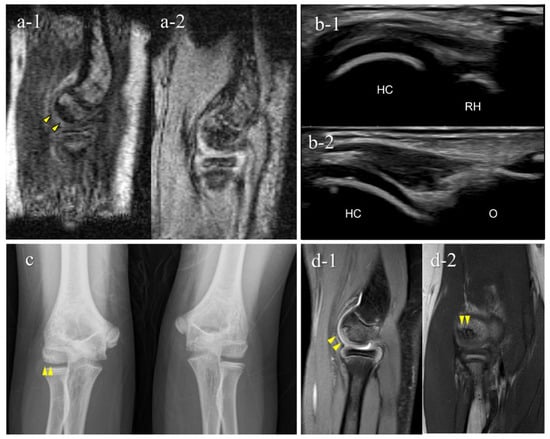

Figure 6. Typical OCD case (Case 3): Mobile MRI (+), US (+). (a) Mobile MR images; a-1, T1WI sagittal image; a-2, T2*WI sagittal image: Mobile MRI depicted the OCD lesion as a low-signal area in a T1WI sagittal image and a high-signal area in a T2* weighted image; (b) US image of the posterior longitudinal view: US showing subchondral bone irregularity; (c) X-p AP view with elbow 45° flexed: X-p 45° showing the lesion with fragmentation, stage II-OCD; (d) 3T MR images: d-1, PDWI sagittal image; d-2, coronal image: localization of the lesion was consistent with that of 3T MRI and mobile MRI.